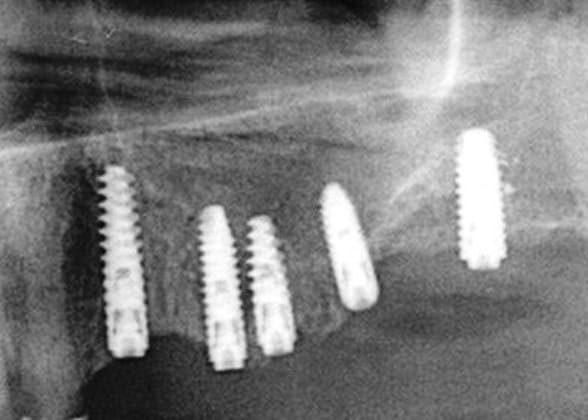

ce n'est pas fait dans l'ordre logique mais après la mandibule, le maxillaire... 12 à cassée (le patient pose sa prothèse pour dormir) donc je ne garde que 11/21/22 et pose d'implants.

Certains vont dire que je ne suis pas économique, mais le all on four ce n'est pas mon truc.

ouarf, mdr, l'implant en 47 est lingualé et tous les autres à partir du secteur antérieur partent sur la droite...comme pour tous les droitiers....

A ce sujet, plutôt que de looker l'axe de 47, jette un œil sur 26 .... il ne s'agit pas de montrer que je suis le meilleur, mais que des techniques simples et bien raisonnées permettent d'obtenir des résultats corrects et reproductible, et ce par n'importe quel dentiste consciencieux.

pour 26 (comme pour les 17 autres implants de ce cas) flapless intégral (même pas de puch), foret initial directement à travers la gencive) et uniquement des éponges de Gelatemp là où c'était nécessaire.